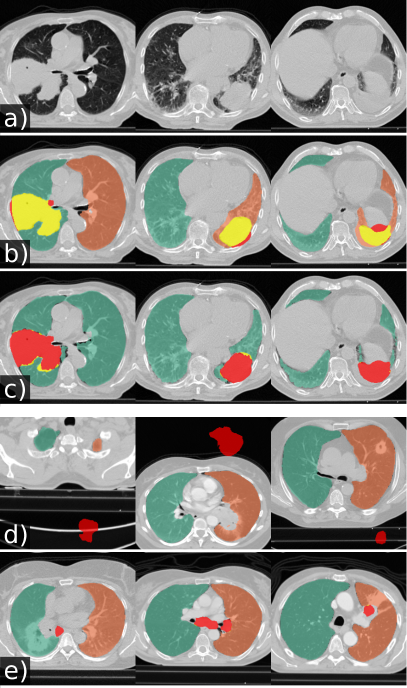

Refer to caption

Figure 5: Qualitative results of automatically generated lung masks for tumor cases. Yellow: tumor area covered by the lung mask. Red: tumor area not covered by the lung mask. (a) Lung masks generated by our U-net(R-213). (b) Lung masks generated by P-HNN. (c) Corrupted tumor segmentations in the Lung1 dataset. (d) Cases with poor tumor overlap of lung masks generated by U-net(R-213).

Models trained on routine data achieve improved evaluation scores compared to models trained on publicly available study data. U-net, ResU-net, and Deeplab v3+ models, when trained on routine data (R-36), yielded the best evaluation scores on the merged test dataset (All, n = 62). The U-net yields mean DSC, HD95, and MSD scores of 0.96 ±plus-or-minus\pm 0.08, 9.19 ±plus-or-minus\pm 18.15, 1.43 ±plus-or-minus\pm 2.26 when trained on R-36 [U-net(R-36)] and 0.92 ±plus-or-minus\pm 0.14, 13.04 ±plus-or-minus\pm 19.04, 2.05 ±plus-or-minus\pm 3.08 when trained on VISC-36 (R-36 versus VISC-36, p = 0.001, 0.046, 0.007) or 0.94 ±plus-or-minus\pm 0.13, 11.09 ±plus-or-minus\pm 22.9, 2.24 ±plus-or-minus\pm 5.99 when trained on LTRC-36 (R-36 versus LTRC-36, p = 0.024, 0.174, 0.112). This advantage of routine data for training is also reflected in results using other combinations of model architecture and training data. Table III lists the evaluation results in detail. We determined that the influence of model architecture is marginal compared to the influence of training data. Specifically, the mean DSC does not vary for more than 0.02 when the same combination of training and test set was used for different architectures (Table III). Compared to readily available trained P-HNN model, the U-net trained on the R-231 routine dataset [U-net(R-231)] yielded mean DSC, HD95, and MSD scores of 0.98 ±plus-or-minus\pm 0.03, 3.14 ±plus-or-minus\pm 7.4, 0.62 ±plus-or-minus\pm 0.93 versus 0.94 ±plus-or-minus\pm 0.12, 16.8 ±plus-or-minus\pm 36.57, 2.59 ±plus-or-minus\pm 5.96 (p = 0.024, 0.004, 0.011) merged test dataset (All, n = 62). For comparison with the CIP-algorithm, only volumes for which the algorithm did not fail were considered. On the merged dataset (All, N=62) the algorithms yielded mean DSC, HD95, and MSD scores of 0.98 ±plus-or-minus\pm 0.01 ,1.44 ±plus-or-minus\pm 1.09 ,0.35 ±plus-or-minus\pm 0.19 for the U-net(R213) compared to 0.96 ±plus-or-minus\pm 0.05, 4.65 ±plus-or-minus\pm 6.45, 0.91 ±plus-or-minus\pm 1.09 for CIP (p = 0.001, <<0.001, <<0.001). Detailed results are given in Table IV. Fig. 2 shows qualitative results for cases from the routine test sets and Fig. 3 shows cases for which the masks generated by the U-net(R-231) model yielded low DSCs when compared to the ground truth. We created segmentations for the 55 cases of the LOLA11 challenge with the U-net(R-231) model. The unaltered masks yielded a mean overlap score of 0.968 and with dense areas removed 0.977. Table V and Fig. 4 show results for tumour overlap on the 318 volumes of the Lung1 dataset. U-net(R-231) covered more tumour volume mean/median compared to P-HNN (60%/69% versus 50%/44%, p << 0.001) and CIP (34%/13%). Qualitative results for tumour cases for U-net(R-231) and P-HNN are show in Figs. 5b, c. We found that 23 cases of the Lung1 dataset had corrupted ground-truth annotation of the tumours (Fig. 5d). Fig. 5e shows cases with little or no tumour overlap achieved by U-net(R-231).

Tumor overlap

Method Mean (%) Median (%) <5%absentpercent5<5\% >95%absentpercent95>95\%

CIP 34 13 113 56

P-HNN 50 44 48 78

U-net(R-36) 53 54 46 79

U-net(R-231) 60 69 37 90

TABLE V: Overlap between lung masks and manually annotated tumour volume in the Lung1 dataset. Given are mean, median, and number of cases with a smaller than 5% overlap and a larger than 95% overlap.